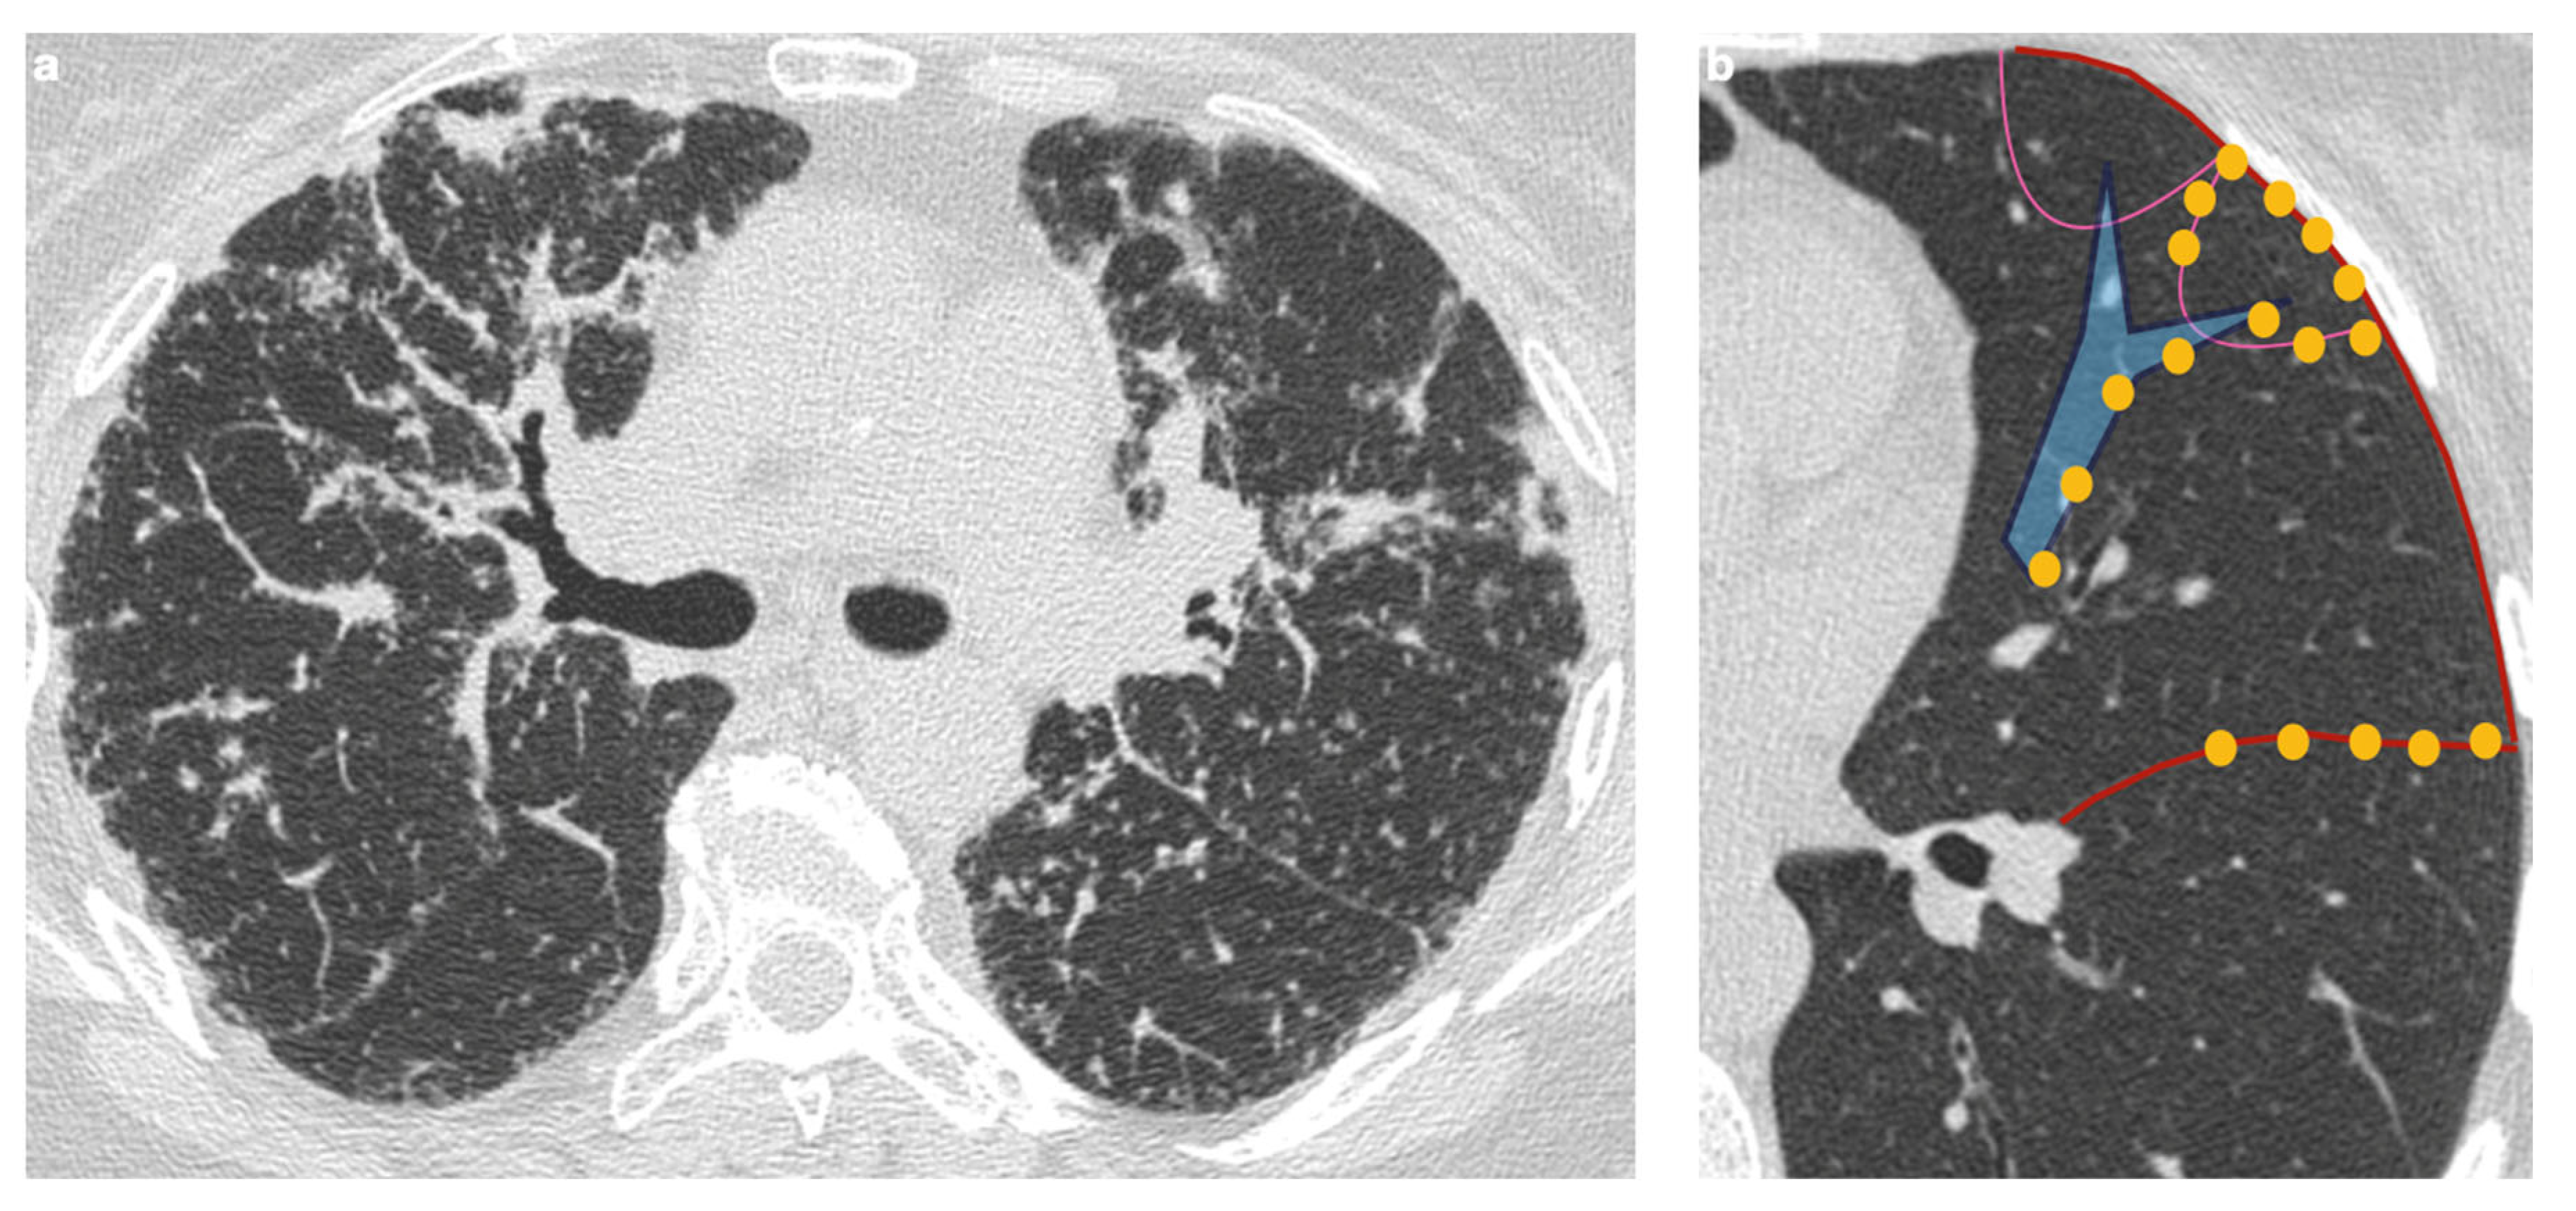

4.1. Typical Imaging

4.2. Atypical Imaging

| Characteristic | Description |

|---|---|

| Distribution | Perilympathic (75–90% of cases); bilateral and symmetric involvement, especially in the middle and upper lobes |

| Nodule size | Micronodules 2–4 mm in diameter |

| Morphology | Nodules with well-defined margins, round shape |

| HRCT localization | Peribronchovascular interstitium, interlobar fissures, interlobular septa |

| Evolution | Possible coalescence of micronodules into macronodules over time |